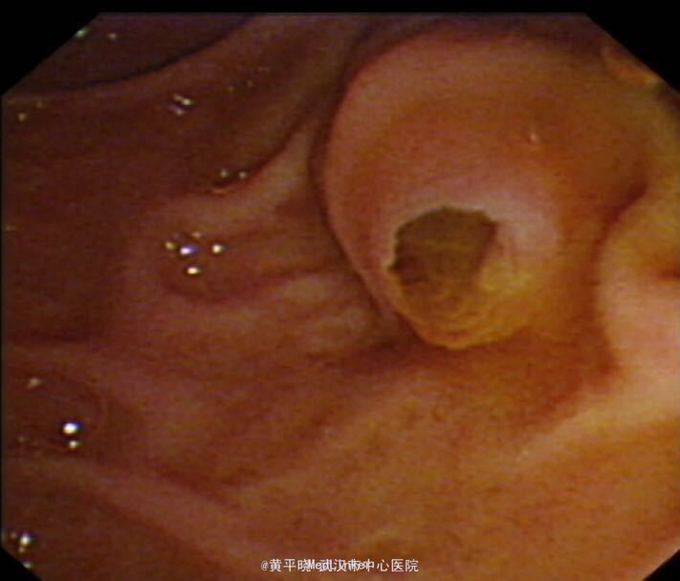

为进一步明确胰管扩张原因及排除有无胆管结石于8月27日行ERCP,术中诊断:1.IPMN(主胰管型?) 2.ERP+ENPD 十二指肠降部中段见乳头,乳头呈乳头型,开口鱼口状扩张,见胶冻样液体流出。 主胰管全程显影,胰头段主胰管及分支胰管明显扩张,主胰管直径约6mm,其内见团块状充盈缺损影,留置鼻胰管,手术经过顺利。 术后鼻胰管可见黏液胶冻样液体引流出 考虑IPMN 转胆胰外科行手术,于2015.09.03行根治性胰十二指肠切除术。 术后病理检查提示:1、(胰头钩突部)符合导管内乳头状粘液性肿瘤伴低-中级别异型增生。 2、(十二指肠)粘膜慢性炎症。 术后经抗感染、静脉及肠内营养、护肝、抑酸、抑酶、补液及维持水电解质酸碱平衡等对症支持治疗,病情恢复良好!